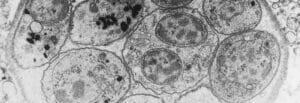

A single-celled parasite called Toxoplasma gondii causes a disease known as toxoplasmosis.